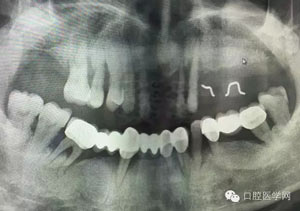

23.jpg

病例1:患者迫切希望保留自己的這一顆牙齒,根尖周陰影比較大,二度松動.而且旁邊有種植修復體,和患者溝通好后,治療好后觀察一個月后冠修復,因為有種植的后期修復,所以有了機會觀察,術后三個月和術后四個月,根尖恢復的還算不錯,希望能夠繼續觀察下去.這樣子的病例,做的時候我們一定要非常的小心,和患者要有充分的溝通以及不同科室的溝通然后決定怎么樣做比較好,假如就是出現了問題,到時候我們也比較好處理些,免得我們自己到時候不好收場。